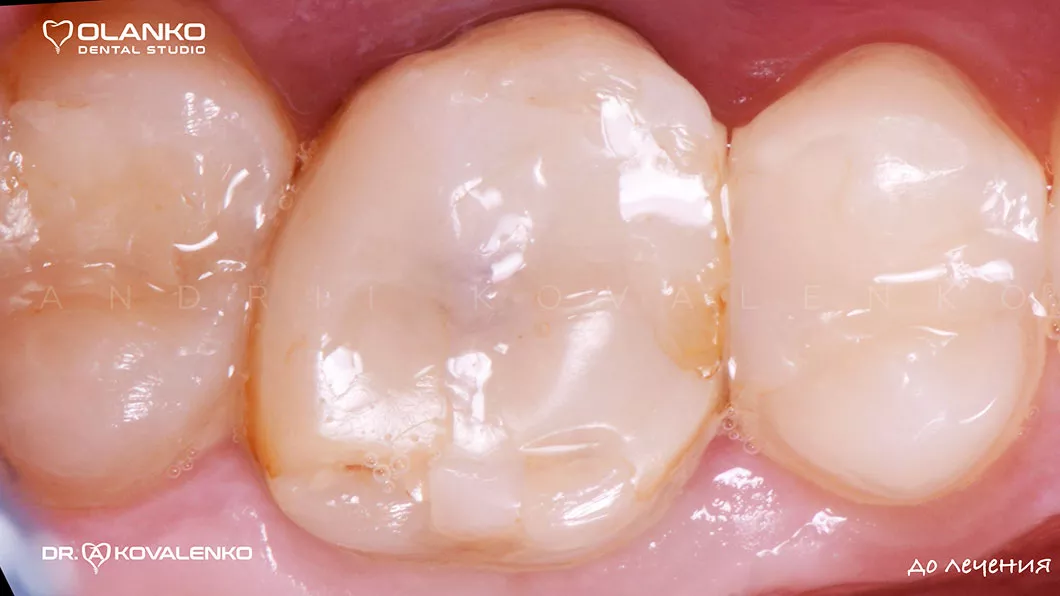

Фото до лікування